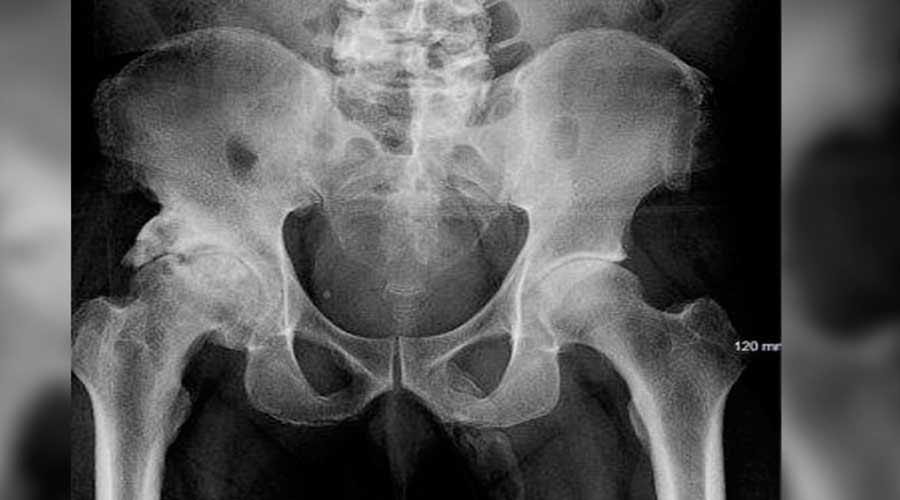

La calcificación del pene es un fenómeno poco común, pero existen otros casos que han sido registrados en la literatura científica